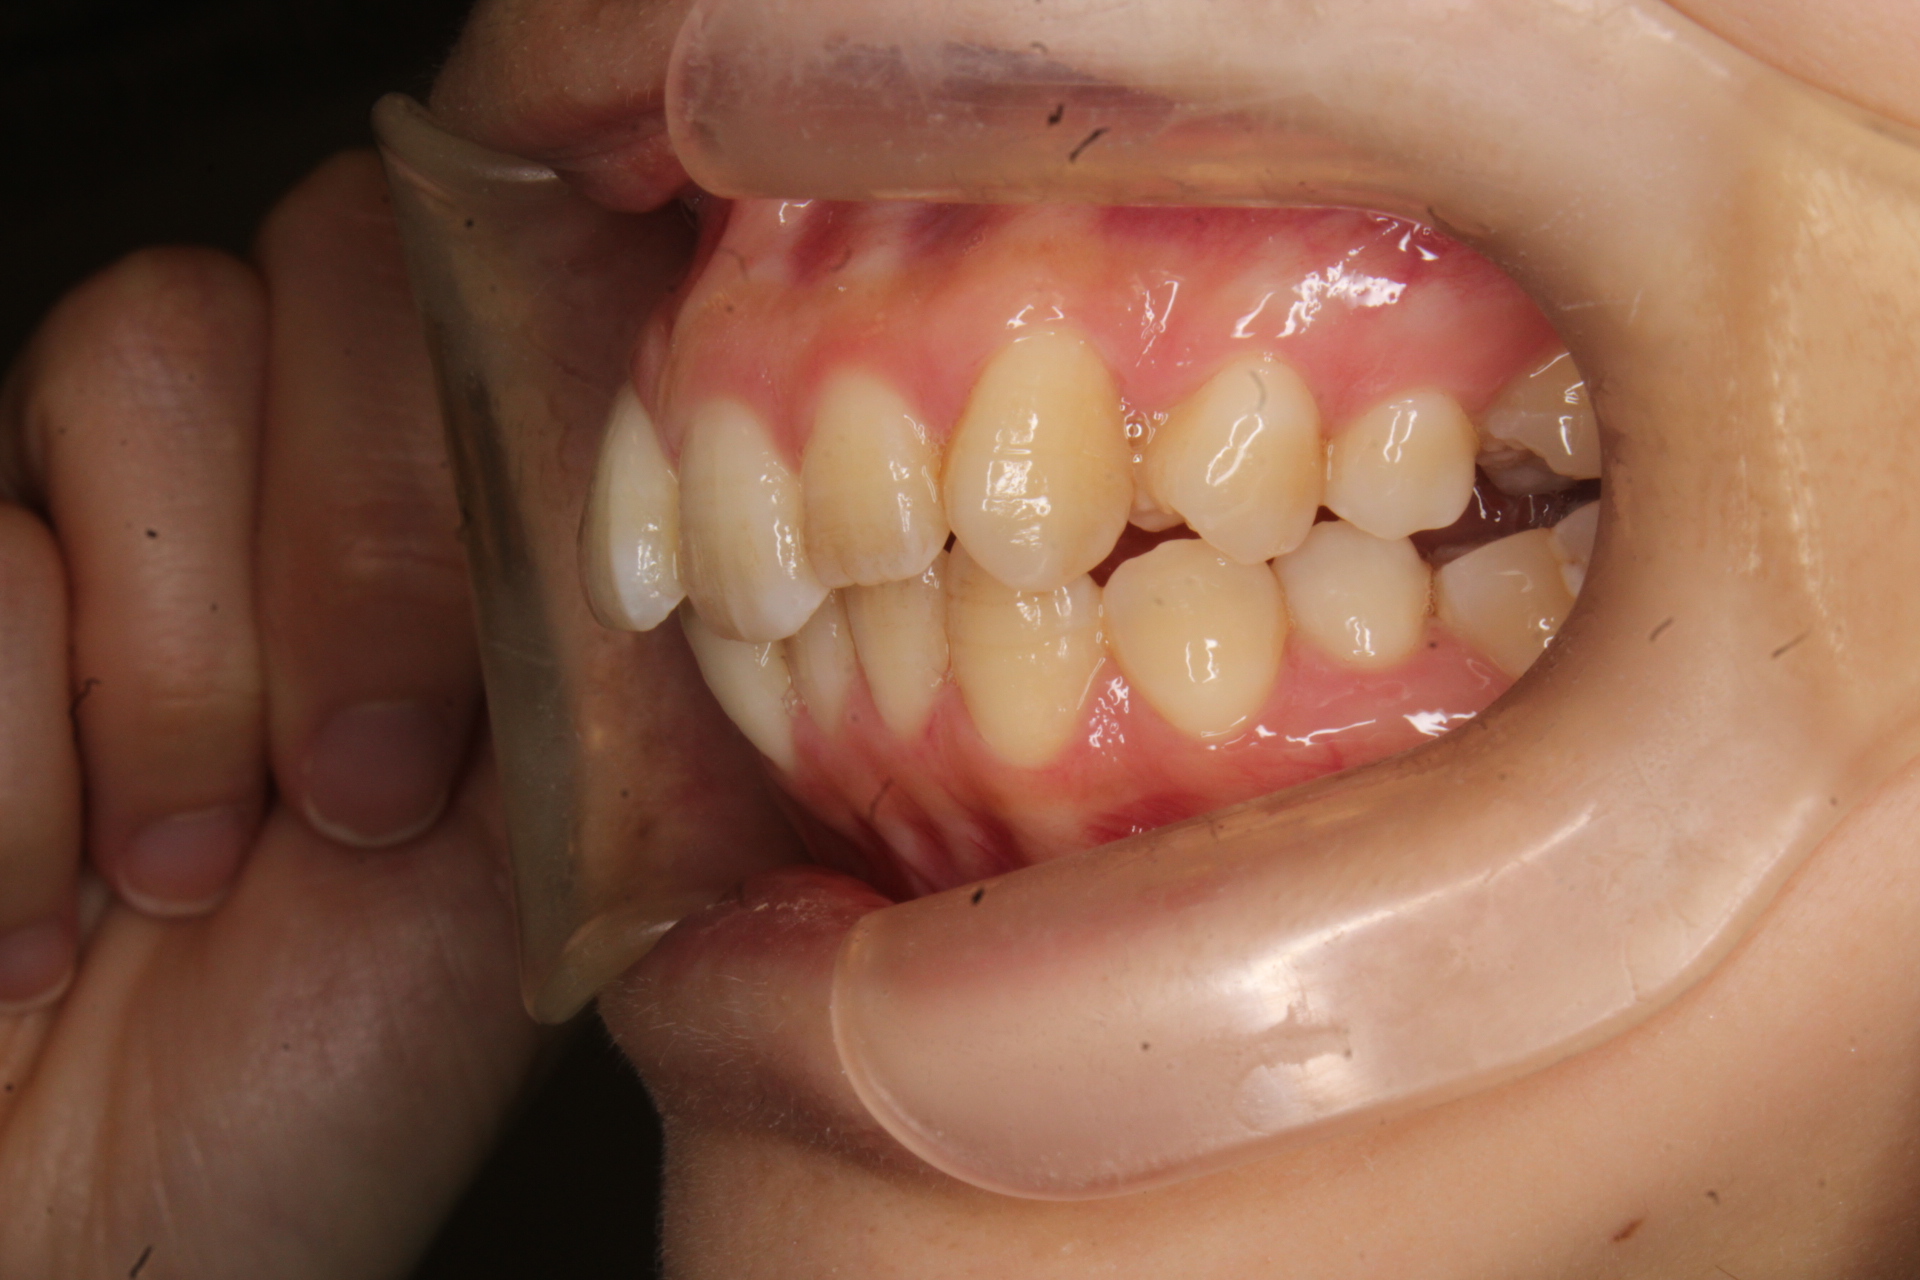

年齢層 20代

性別 男性

主訴 【主訴】出っ歯を治したい 【診断・症状】上下凸凹、出っ歯(上顎前突)

治療費用 検査・診断:38,500-/裏側矯正治療:1,397,000-(※全て税込)

治療期間 約1年半(20回)

抜歯 有(上4,4のみ)

矯正の装置 裏側矯正(舌側矯正)

副作用、リスク 歯肉退縮,歯根吸収,疼痛,咬合の違和感,装置の違和感,虫歯,歯肉炎

case15_出っ歯_before

Before

case15_出っ歯_after

After